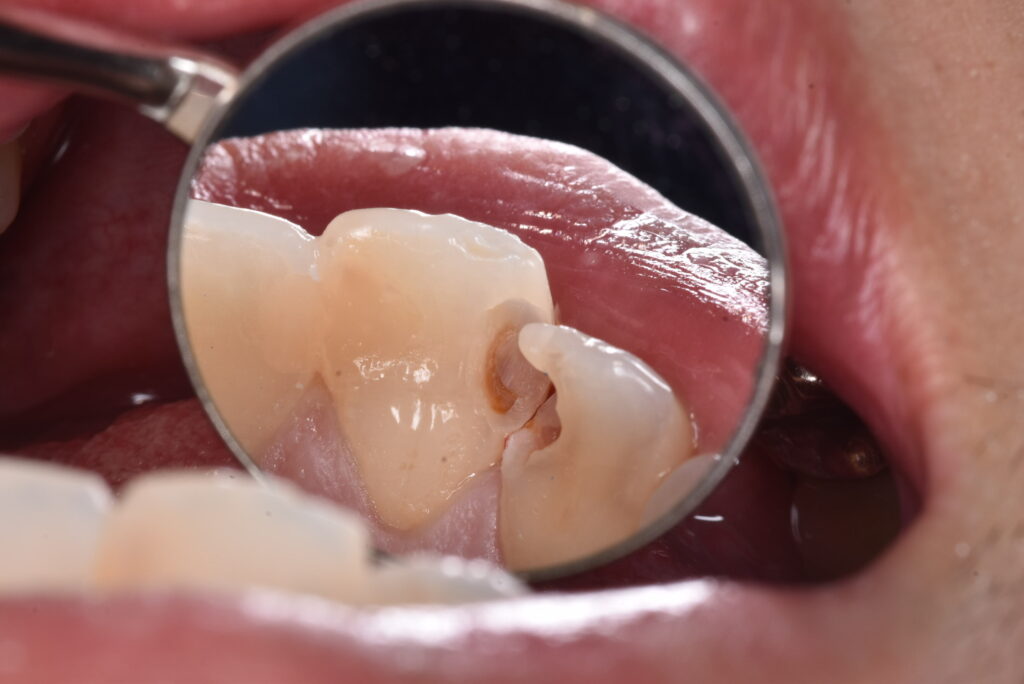

白のつめもののなかの一例

実際の処置例をお見せしていきます。。

処置する前から、怪しい状態なのはなんとなくわかると思います。では、この方は症状はあったのか?

→Noです。ありませんでした。つめものの周りに隙間があったのか?それもNoです。

削った写真を見ていただくと、中で汚染されている部分がわかると思います。一番最後の写真の中央にあるのは、むし歯の部分ではなく、神経の入り口です。神経は基本的に歯の奥の方に隠れています。むし歯を取り除くとそれが見える・・・それは正常なことなのでしょうか?